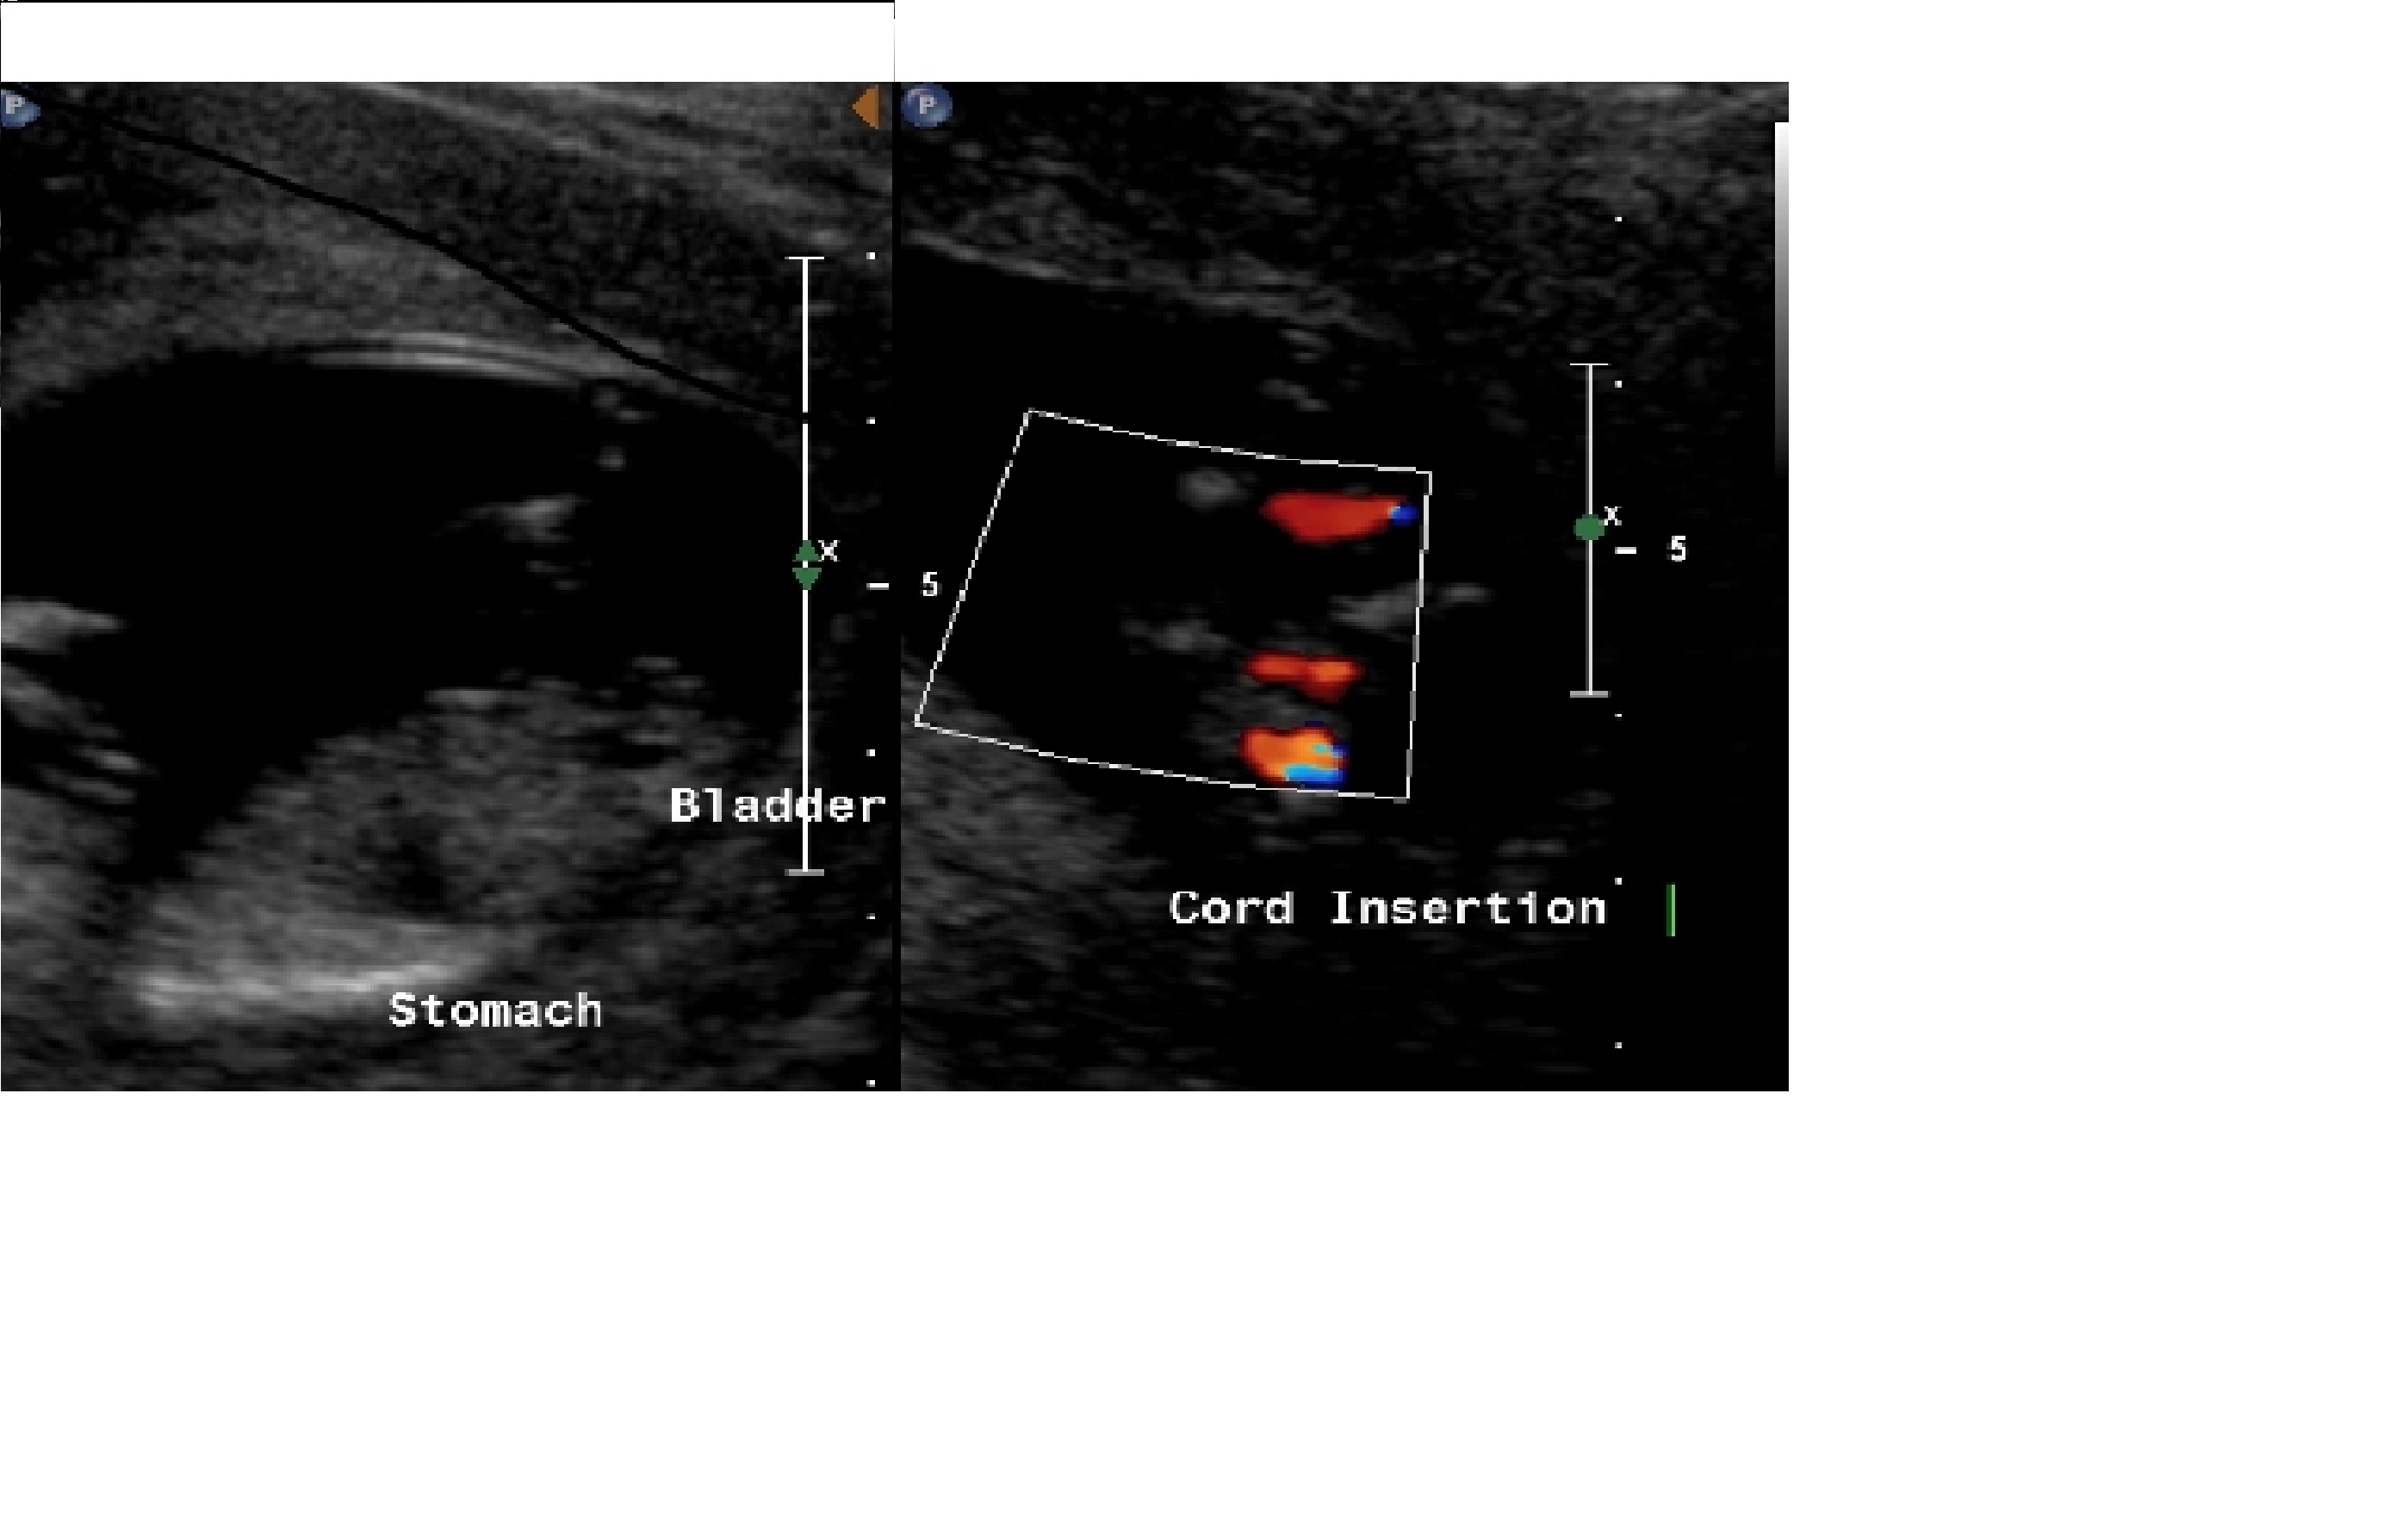

Please tell me your gender guesses based on these ultrasound images from my 12w4d scan.

Attachment 7308Attachment 7309

In the last photo it looks like there's a nub leaning upwards. I'd guess a boy if that is indeed the nub.

looks boy to me, from what I can see it seems to point up a bit